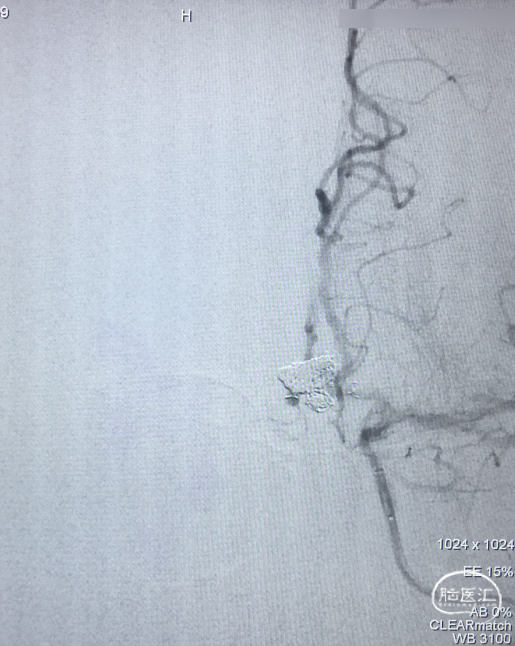

术前DSA 3D:左颈内动脉正侧位及工作位,前交通动脉瘤,约4×8mm,颈宽约6.5mm,形态宽颈、分叶。前交通动脉及大脑前动脉A1、A2直径约2mm。

术前DSA:LICA正侧位及工作角度造影显示前交通动脉瘤

术前DSA:RCCA正侧位造影